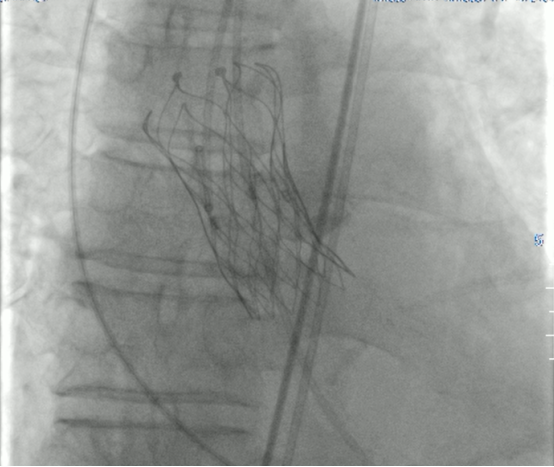

按照術(shù)前詳細(xì)制定的手術(shù)方案,麻醉科、超聲科、影像科“瓣膜團(tuán)隊(duì)”全力協(xié)作,8月15日手術(shù)如期進(jìn)行,經(jīng)股動(dòng)脈順利完成主動(dòng)脈瓣置換手術(shù),患者胸悶憋喘等情況明顯改善,至此首例TAVR圓滿成功。

什么是TAVR?經(jīng)導(dǎo)管主動(dòng)脈瓣置換術(shù)(TAVR)是通過股動(dòng)脈送入介入導(dǎo)管,將人工心臟瓣膜輸送至主動(dòng)脈瓣區(qū)打開,從而完成人工瓣膜置入,恢復(fù)瓣膜功能。該技術(shù)具有創(chuàng)傷小、恢復(fù)快、安全性高,并發(fā)癥少的優(yōu)點(diǎn),對(duì)于心功能衰竭的重度主動(dòng)脈瓣狹窄患者,藥物治療效果差、外科開胸手術(shù)難以耐受,TAVR已成這類患者的“救命神招”!